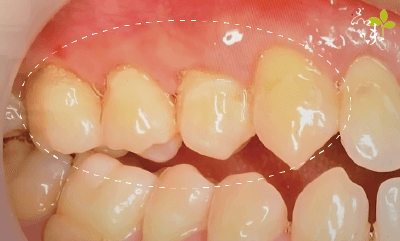

「冬天吃火鍋、夏天喝飲料,牙齒總是痠痛敏感,後來我才注意到,牙齒下方的牙肉消失了,露出黃黃的一截,以為是生病了,才趕快來掛號檢查。」你也有過類似的經驗嗎?很多人大約從20幾歲開始,就有牙齦萎縮的困擾了。這篇文章我們想跟你分享的是牙齦萎縮的成因,以及改善的方法。

牙齒剛生長出來時,牙根是被牙肉緊緊包圍的,只有上部的牙冠會露出牙肉表面。

某天,牙肉開始「倒退」、「減少」,讓牙根逐漸裸露出來,照鏡子一看感覺牙齒變長了──可能就是我們常講的「牙齦萎縮」現象。

要怎麼改善牙齦萎縮?

牙齦萎縮手術補救